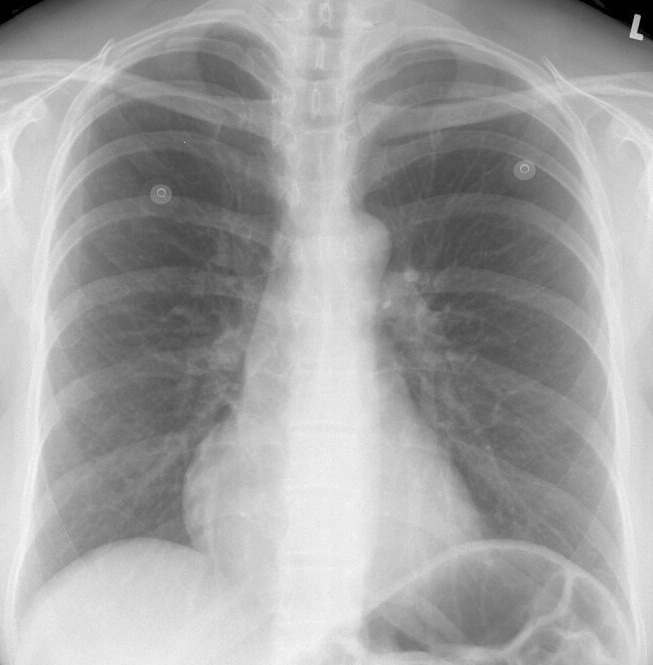

Mesocardia